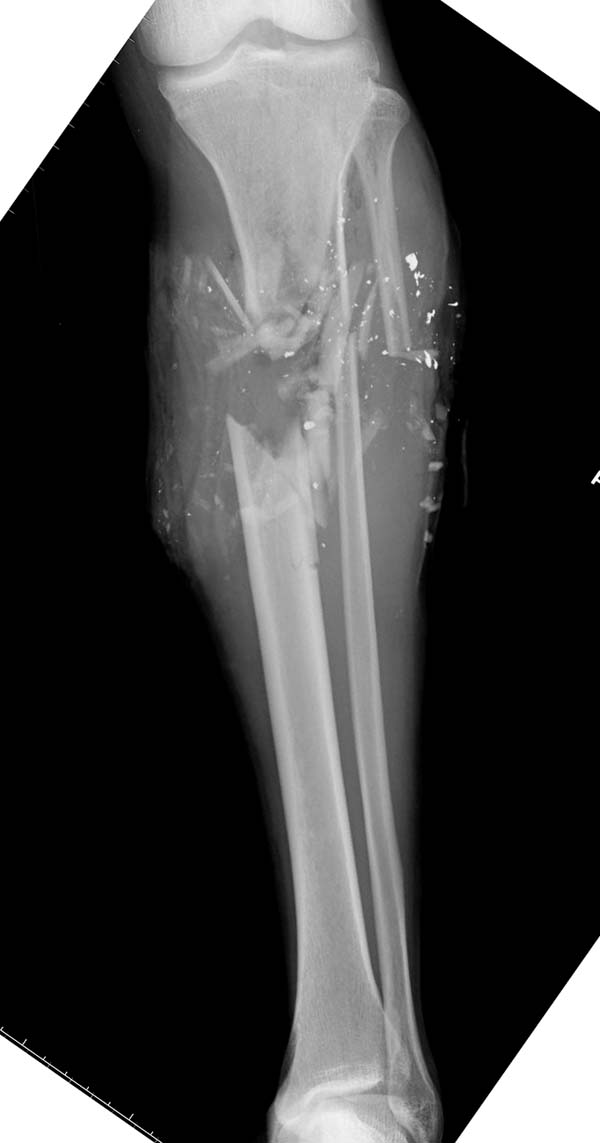

Имя     : 1 gsw tibia ap injury.jpg

Url     : http://weborto.net:8080/pipermail/ortho/attachments/20150717/eea7e369/attachment-0014.jpg